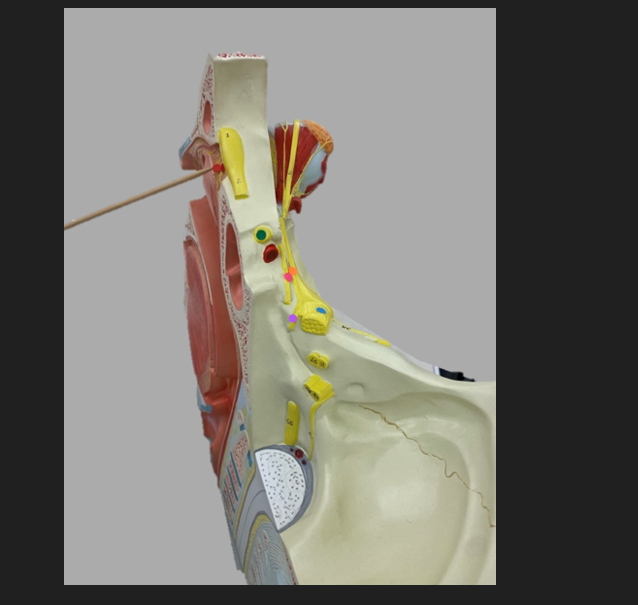

green dot

spinal nerve

orange dot

ventral root

pink dot

dorsal root

blue dot

dorsal root ganglion

red dot

dorsal ramus

yellow dot

ventral ramus

purple dot

anterior median fissure

red dot

posterior (dorsal) horn

purple dot

lateral horn

dark blue dot

anterior (ventral) horn

orange dot

dorsal column

yellow dot

lateral column

dark green

anterior column

line green and pink doit

gray commissure

light blue dot

posterior median sulcus